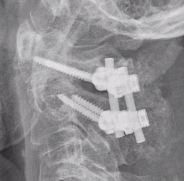

1. Transarticular screws (Magerl)

2. C1 lateral mass / C2 pedicle screws (Goel-Harms)

+/- Brooks interlaminar wire with posterior bone graft

C1 lateral mass / C2 pedicle screws (Goel Harms)

Transarticular / Magerl screws from: Koepke et al Nature Reports